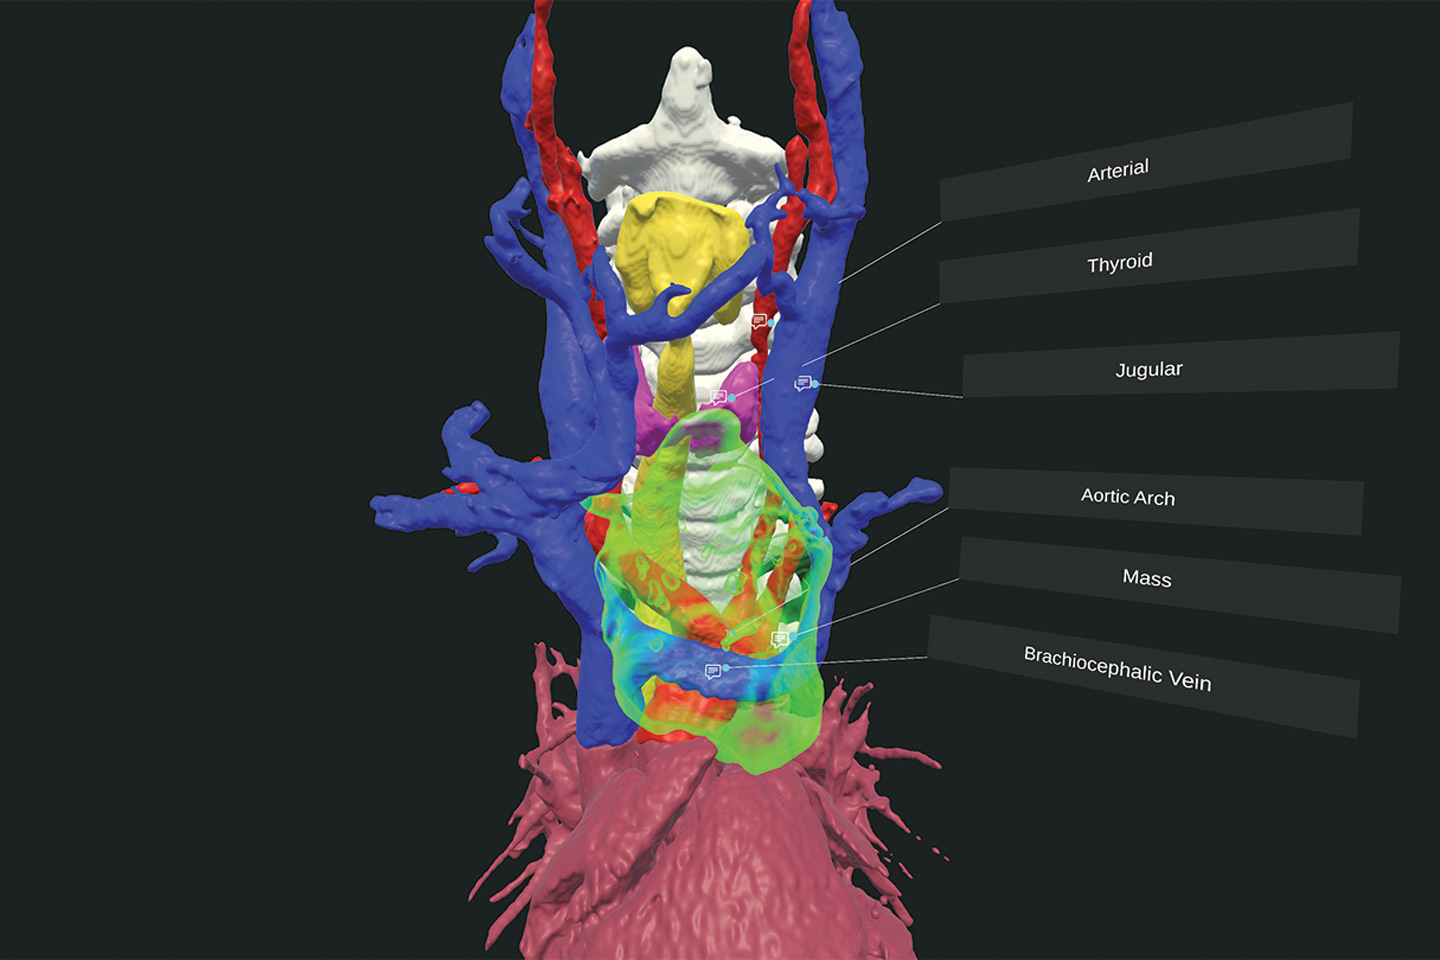

Virtual reality rendering providing a 3D view of the tumor and its relationship to surrounding anatomy. Source: NYU Langone Health.

Preoperative planning was aided by advanced virtual reality visualization and the cardiac imaging expertise of Puneet Bhatla, MD. “We prepared for every scenario, from vascular reconstruction to emergency support, so that once the chest was open, we could proceed confidently and safely,” says Dr. Kumar.

Virtual reality visualization of the tumor’s position near critical structures. Source: NYU Langone Health.